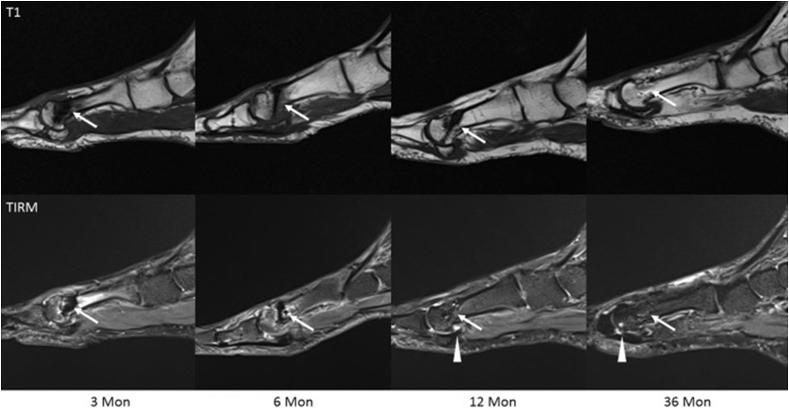

Magnesium-based implants are re-emerging as a substantial amendment to standard orthopaedic implants. A brief introduction of magnesium (Mg) as a biodegradable material and basic magnetic resonance imaging (MRI) principles are discussed. This review aims to highlight the current performance of these implants during examinations with MRI. We also aim to summarise comparisons between Mg-based implants with current standards to emphasise the promotion of biodegradable implants in clinical practice. A comprehensive search of current literature on Mg-based implants and the utilisation of MRI in the studies was performed. Additionally, recorded artefact behaviour of Mg-based implants during MRI was investigated. A total of nine studies were included in which MRI was employed to image Mg-based implants. Of those studies, four of the nine discuss artefact production caused by the implants. MRI successfully imaged regions of interest over all and produced fewer artefacts than other materials used in the studies. MRI was employed in contrast angiography, bone growth observation, bone infection healing, and blood perfusion. Imaging capabilities of an implant material are vital to translating products into clinical application. Positive findings presented in this review suggest and support the use of Mg-based implants due to their successful visual compatibility with MRI techniques.

镁基植入物正作为标准骨科植入物的一项重大改进而重新兴起。本文讨论了作为可生物降解材料的镁(Mg)的简要介绍以及基本的磁共振成像(MRI)原理。本综述旨在突出这些植入物在MRI检查期间的当前性能。我们还旨在总结镁基植入物与当前标准之间的比较,以强调可生物降解植入物在临床实践中的推广。对当前关于镁基植入物的文献以及研究中MRI的应用进行了全面检索。此外,还研究了镁基植入物在MRI期间记录的伪影行为。总共纳入了九项使用MRI对镁基植入物进行成像的研究。在这些研究中,九项中有四项讨论了由植入物引起的伪影产生。MRI成功地对所有感兴趣区域进行了成像,并且产生的伪影比研究中使用的其他材料更少。MRI被用于对比血管造影、骨生长观察、骨感染愈合和血液灌注。植入材料的成像能力对于将产品转化为临床应用至关重要。本综述中呈现的积极结果表明并支持使用镁基植入物,因为它们与MRI技术具有成功的视觉兼容性。